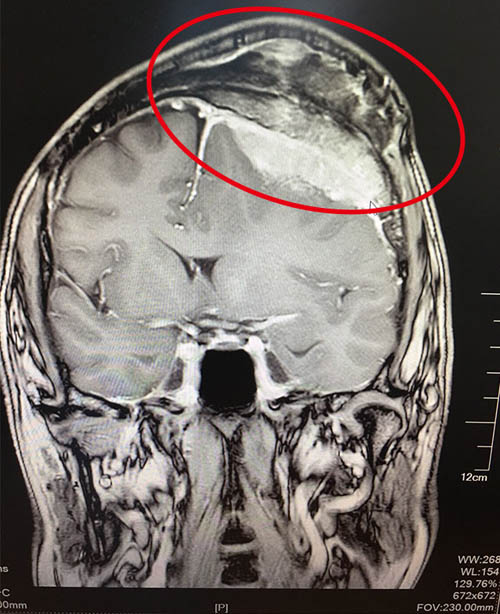

2、CT扫描:在脑膜瘤的诊断上,CT扫描已取代同位素脑扫描、气脑和脑室造影、脑膜瘤多为实质性且富于血运,适合于CT检查,其准确性能够达到发现1cm大小的脑膜瘤。在CT扫描图像上,脑膜瘤有其特殊征象,在颅内显示出局限性圆形密度均匀一致的造影剂增强影像,可并有骨质增生,肿瘤周边出现密度减低的脑水肿带,相应的脑移位,以及脑脊液循环梗阻引起的脑积水征象。